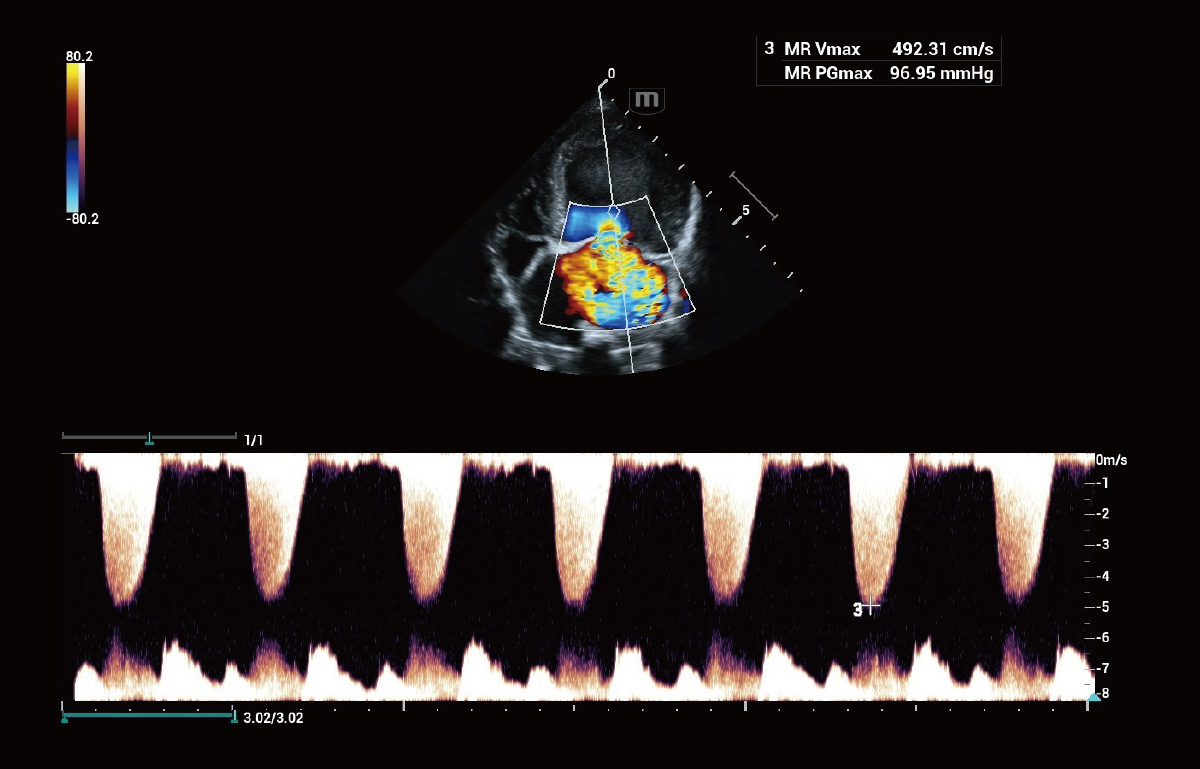

组织多普勒定量分析 TDI QA

全面的组织多普勒成像模式(TVI,TVD,TVM,TEI),支持多达8个ROI的心肌运动同步性分析,为医生提供多维度的心脏组织运动参数。